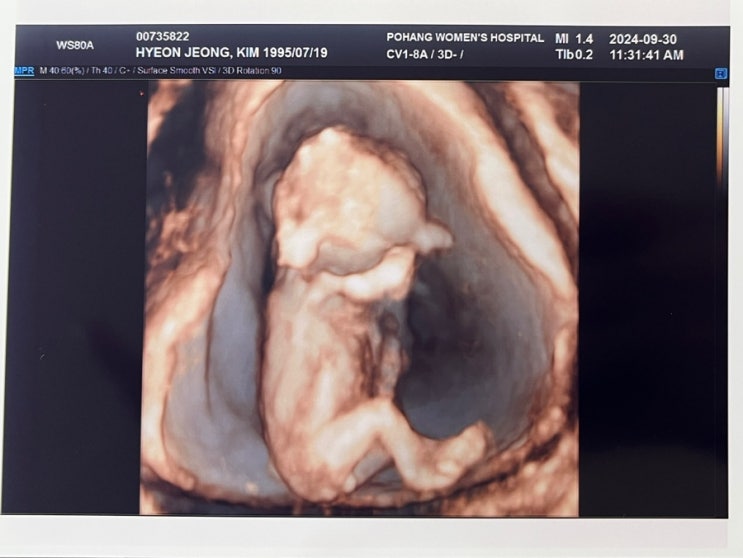

[12W] 부끄럼 많은 꽃복이

드디어 병원가는 날 4주에 1번씩 가니 너무 궁금해서 미쳐버릴거같음 꽃복이는 잘 있는지.. 얼마나 컷는지....